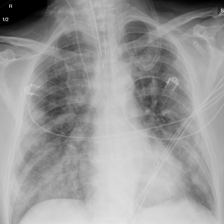

Fig. 7: Medical image segmentation from QaTa-COV19 dataset. The text annotations are created by hand-craft.

QaTa-COV19: This dataset from Tampere University and Qatar University contains 121,378121378121,378 chest X-ray images (CXRs), including 9258 coronavirus disease 2019 (COVID-19) samples. Each image has a corresponding ground-truth mask for COVID-19 pneumonia segmentation. We choose 50 images as our training set and 10 images as our testing set. In addition, we create the text annotations for this datasets.

Fig. 7 shows the results obtained from experiments on the QaTa-COV19 datasets. Closer inspection of the figure shows that MedT has superiority in depicting long-range information. This benefits from the gated parameters. They can control the amount of information that the positional embedding supplies to key, query and value. It is noteworthy that its ability to learn the local features can still be enhanced.

GTUNet still has trouble capturing local features and depicting the exact edge shape. Inferior to GTUNet, SwinUNet can only produce rough infected regions. However, as shown in Fig. 7, it struggles to catch local details, so some incorrect areas are delineated, and the edge depiction is coarse.

UCTransNet and LViT increase their segmented accuracy. We can observe that they depict the correct infected regions of the first and second IMGs in Fig. 7. What stands out in their result pictures is that they cannot give precise edge information.

Compared with other networks, our model integrates Transformer and CNN into PPE, which ensures that it can obtain meaningful representations. After it has these powerful abilities, we combine PPE and the downstream segmentation tasks. Owing to the pretrained phase and the well-designed decoder, our model presents the most exact segmented results.